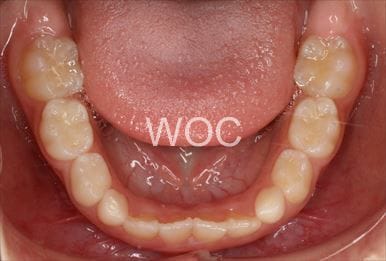

治療前1

-

治療前2

-

治療前3

- 年齢:27歳女性

- 主訴:上下のずれ

- 基本矯正料金:105万円

- 治療期間:2年3ヶ月

- 抜歯部位:上顎右側第二小臼歯、下顎右側第一小臼歯

-